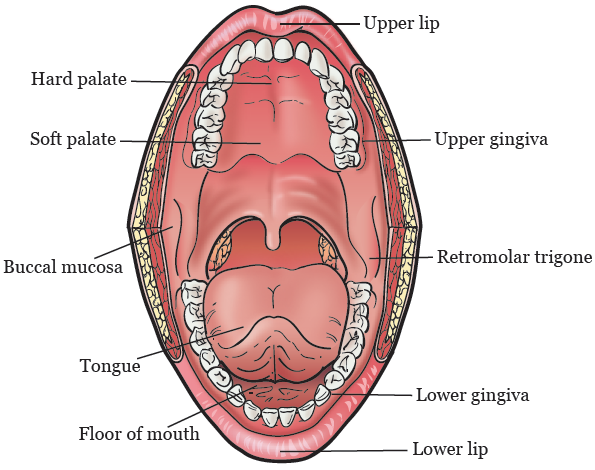

Oral Cancer Mouth Cancer Anatomy Headandneckcancerguide Org

Oral Cancer Wikipedia

Cancers Of The Floor Of The Mouth

Floor Of The Mouth Cancer

Floor Of The Mouth Cancer Causes Symptoms Treatment Survival

Malignant Tumors Of The Floor Of The Mouth Background

Cancers Of The Floor Of The Mouth

Cancers Of The Floor Of The Mouth